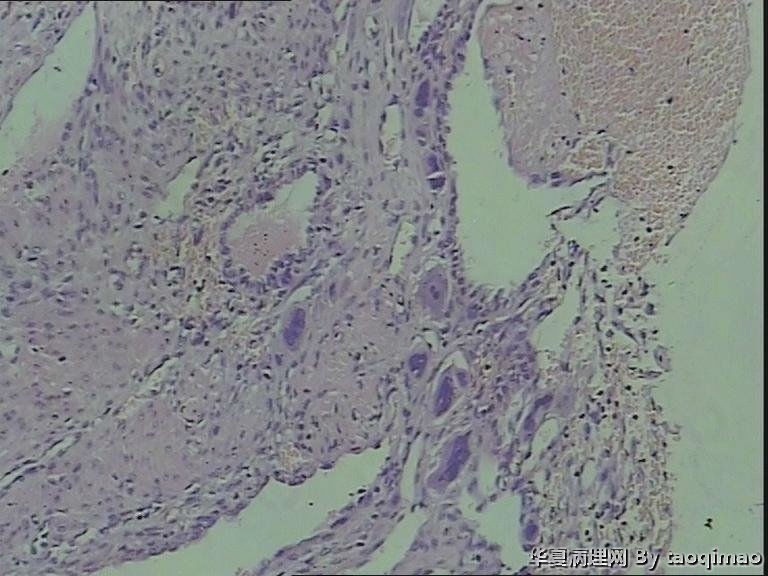

• 功血,滋养细胞浅肌层?图1

图1

这是患者第一次刮宫的内膜,怎么出报告呢

追问病史 除外绒癌 侵袭性葡萄胎

上一组图是全子宫切除后宫内膜及浅肌层的切片,取材时发现在子底及后壁有暗紫色血凝块与宫内膜分界不清

患者资料:39岁女,阴道不规则出血,2011,6,诊刮可见:内膜腺体囊性增生,现再次出血诊刮术。术中子宫后位,宫深9cm,子宫增大内膜不平,刮出内膜组织约2g。红褐色破碎组织一堆大小3X2.5cm,质软。